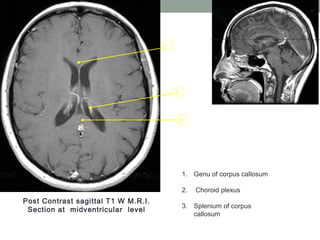

Post Contrast sagittal T1 W M.R.I.

Section at midventricular level

1. Genu of corpus callosum

2. Choroid plexus

3. Splenium of corpus

callosum

3 2 1 Post Contrast sagittalT1 W M.R.I. Section at midventricular level 1. Genu of corpus callosum 2. Choroid plexus 3. Splenium of corpus callosum